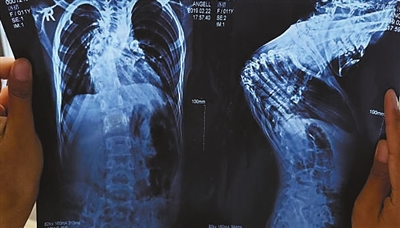

洛措术前检查。

几年前,洛措的脊柱开始出现病变:先是患上脊柱结核,继而出现侧弯、后凸,最后,她的上半身仿佛被一股无形的力量狠狠拧了一把。

宁尚龙后来在分析病情时,用了一个形象的比喻:“洛措的脊柱出现了三维的折叠错位,它不只是纵向移位,还有螺旋式的扭曲——胸段4到9节这6个椎体,成了一个死疙瘩。”

这个“死疙瘩”不仅压迫着洛措的脊髓和神经,更挤压着她的胸腔,导致肺叶萎缩,心脏和主动脉扭曲缠绕,而那条维系着运动功能的脊髓,被深埋在畸形的椎管里,薄如蝉翼,稍有不慎就会出现损伤。同时,她还是乙肝大三阳感染者。多重因素叠加,使得手术的复杂程度极高,国内几乎无成功先例。